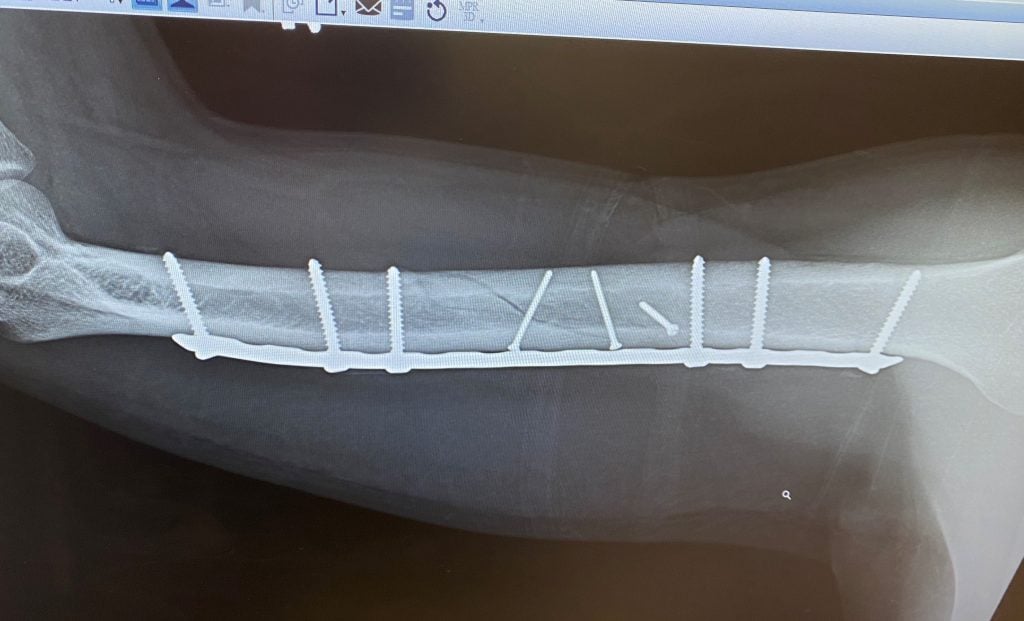

While out jogging one morning in October 2015, I was involved in a hit and run. Emergency Medical Technicians took me to a local hospital where I was diagnosed with a shattered humerus. We decided we only wanted the best care for such a traumatic injury so we got in touch with Esther Shin at Dr. Helfet's office. They could not have been any nicer and accommodating. The entire hospital staff were just amazing from the instant we rolled through the doors through out the entire stay, which was for almost a week. The humerus needed to be put back together with a couple of pins and many screws, as well as the muscle needing to be reconstructed.